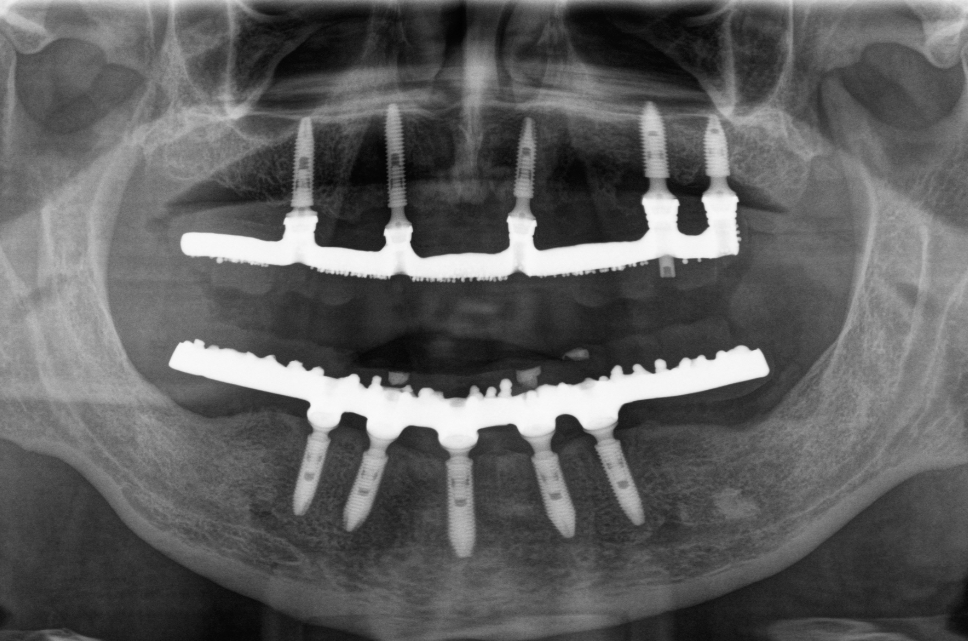

Protocolo

As Próteses tipo Protocolo são as soluções mais utilizadas com implantes para desdentados totais, são Próteses Fixas parafusadas nos implantes dando ao paciente uma sensação de estabilidade total. Tradicionalmente são utilizados de 6 a 8 Implantes no arco superior e 3 a 6 no inferior. A prótese possui uma barra metálica sobre a qual os dentes são aplicados, podendo, os dentes,  serem de cerâmica ou resina. No caso do protocolo cerâmico, a barra metálica pode ser substituída por Zircônia (100% em Cerâmica).

Esta modalidade de tratamento devolve ao paciente a capacidade mastigatória absoluta, com um resultado estético extremamente satisfatório já que repõe gengiva e dentes e tudo pode ser escolhido pelo dentista como: coloração, tanto gengival quanto dental; tamanho; formato e posição dos dentes.